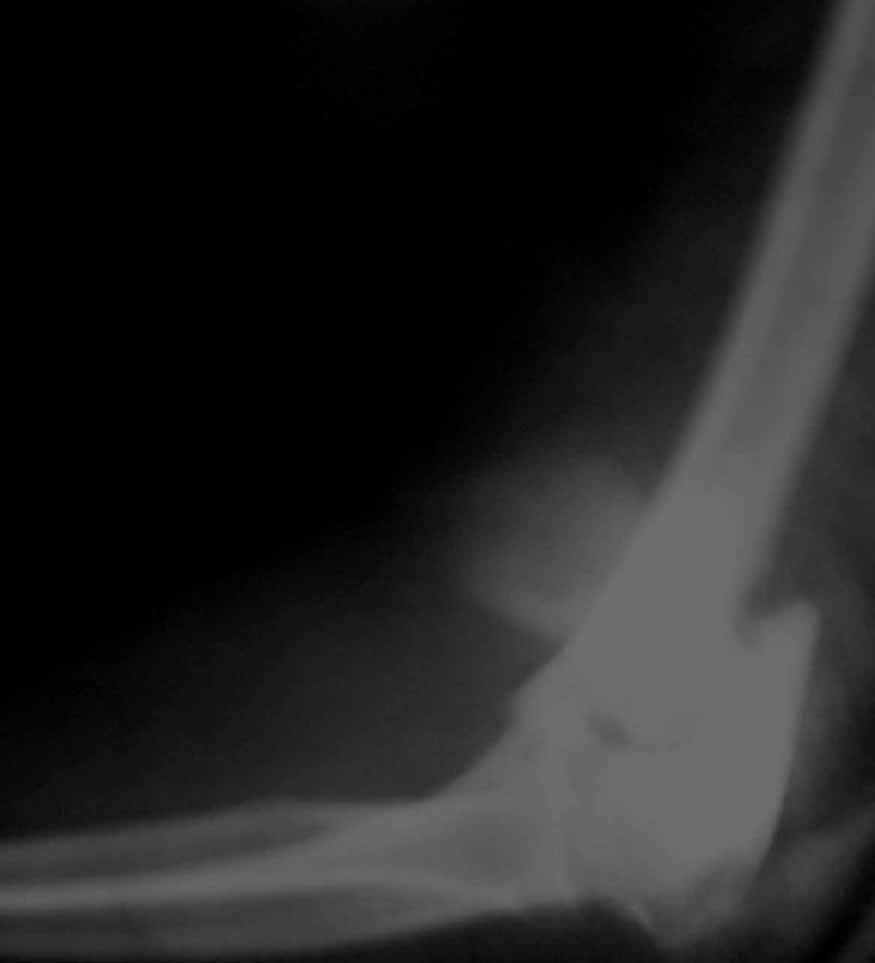

Женщина 42 лет, операция через неделю после перелома.

Д-з - открытый перелом мыщелков со смещзением и локтевой кости

без смещения - падение с лошади.

До операции снимки не очень, тем более в гипсе.